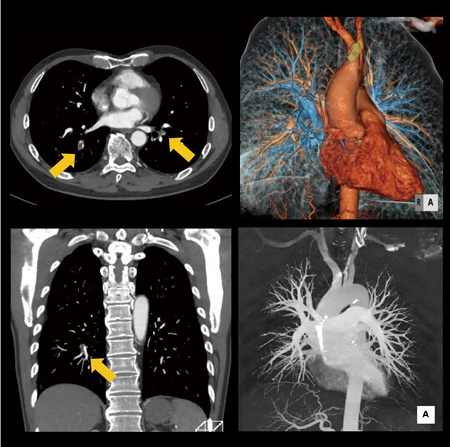

【背 景】左下腹部痛を主訴に来院。疼痛は下腹部痛から右下腿痛に,その後,吸気時の背部痛へと徐々に変化。CT撮影後,PTE(肺血栓塞栓症)と診断され,後日IVCフィルター挿入。

【所 見】両側肺動脈の下葉枝に血栓と考えられる低吸収域が明瞭に描出され,肺血栓塞栓症と診断。肺動脈末梢側まで良好に描出され,VR画像においてはワークステーション上で動脈と静脈の分離が可能。

【ポイント】(1)造影剤の注入方法を工夫(24mgl/kg/s×10s固定注入→生食20mL後押し→10mL/s×残り造影剤量→5分後に足から頭方向に向かって下肢の撮影),(2)撮影タイミング<目視>(プレモニタリングの位置と撮影スタートのタイミングが非常に重要:肺動脈,上大静脈,上行大動脈が観察できるレベルを選択,サイクルタイム1秒,スキャンディレイタイムは5秒後に設定→造影剤注入開始から約7〜8秒で上大静脈のCT値が上昇。次のスキャンで肺動脈のCT値が軽度上昇していることを確認し撮影スタート),(3)CARE kVの半自動機能を使用して80kVを使用することでコントラストの向上を達成,(4)低管電圧を使用することによるノイズ量の増加は,SAFIREを用いて改善。